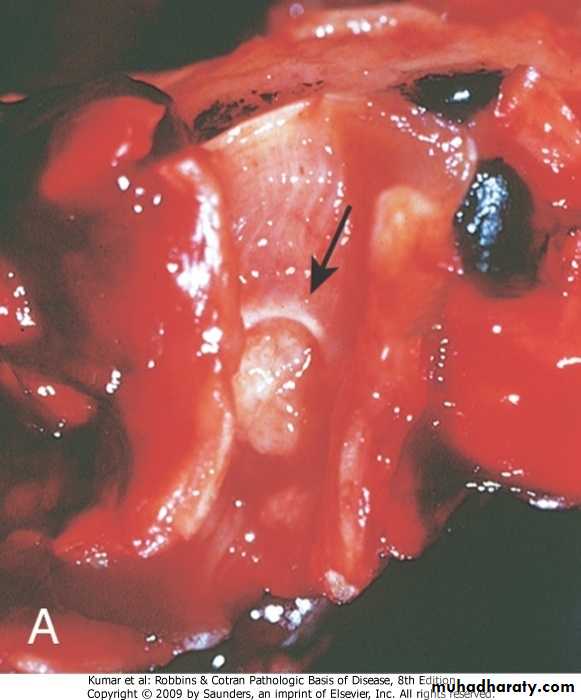

Obstraction → Resorption of air → accumulat ion of secretions & stasis → infection which damage the wall of the bronchi→ Dilatation by intraluminal pressure or traction by the negative pressure of the pleuraBronchiectasis :Pathology

Gross:It may affects any part of the lung but the basal segments are commonly involved

The dilatation may be Cylindrical (involve all the circuference ) or Sacular (involve part of the circumferences),

Bronchogram demonstrate the dilatation nicely